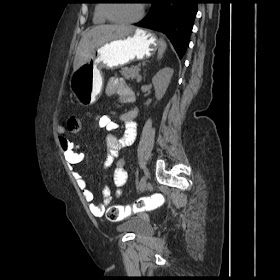

A 70 years old woman with Obstractive jaundice & palpable GB

Latest Radiological images: